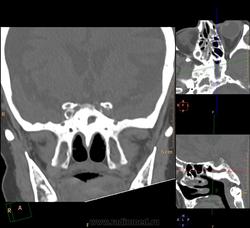

Спонгиоз одной из половин пазухи, пациент 35 лет: